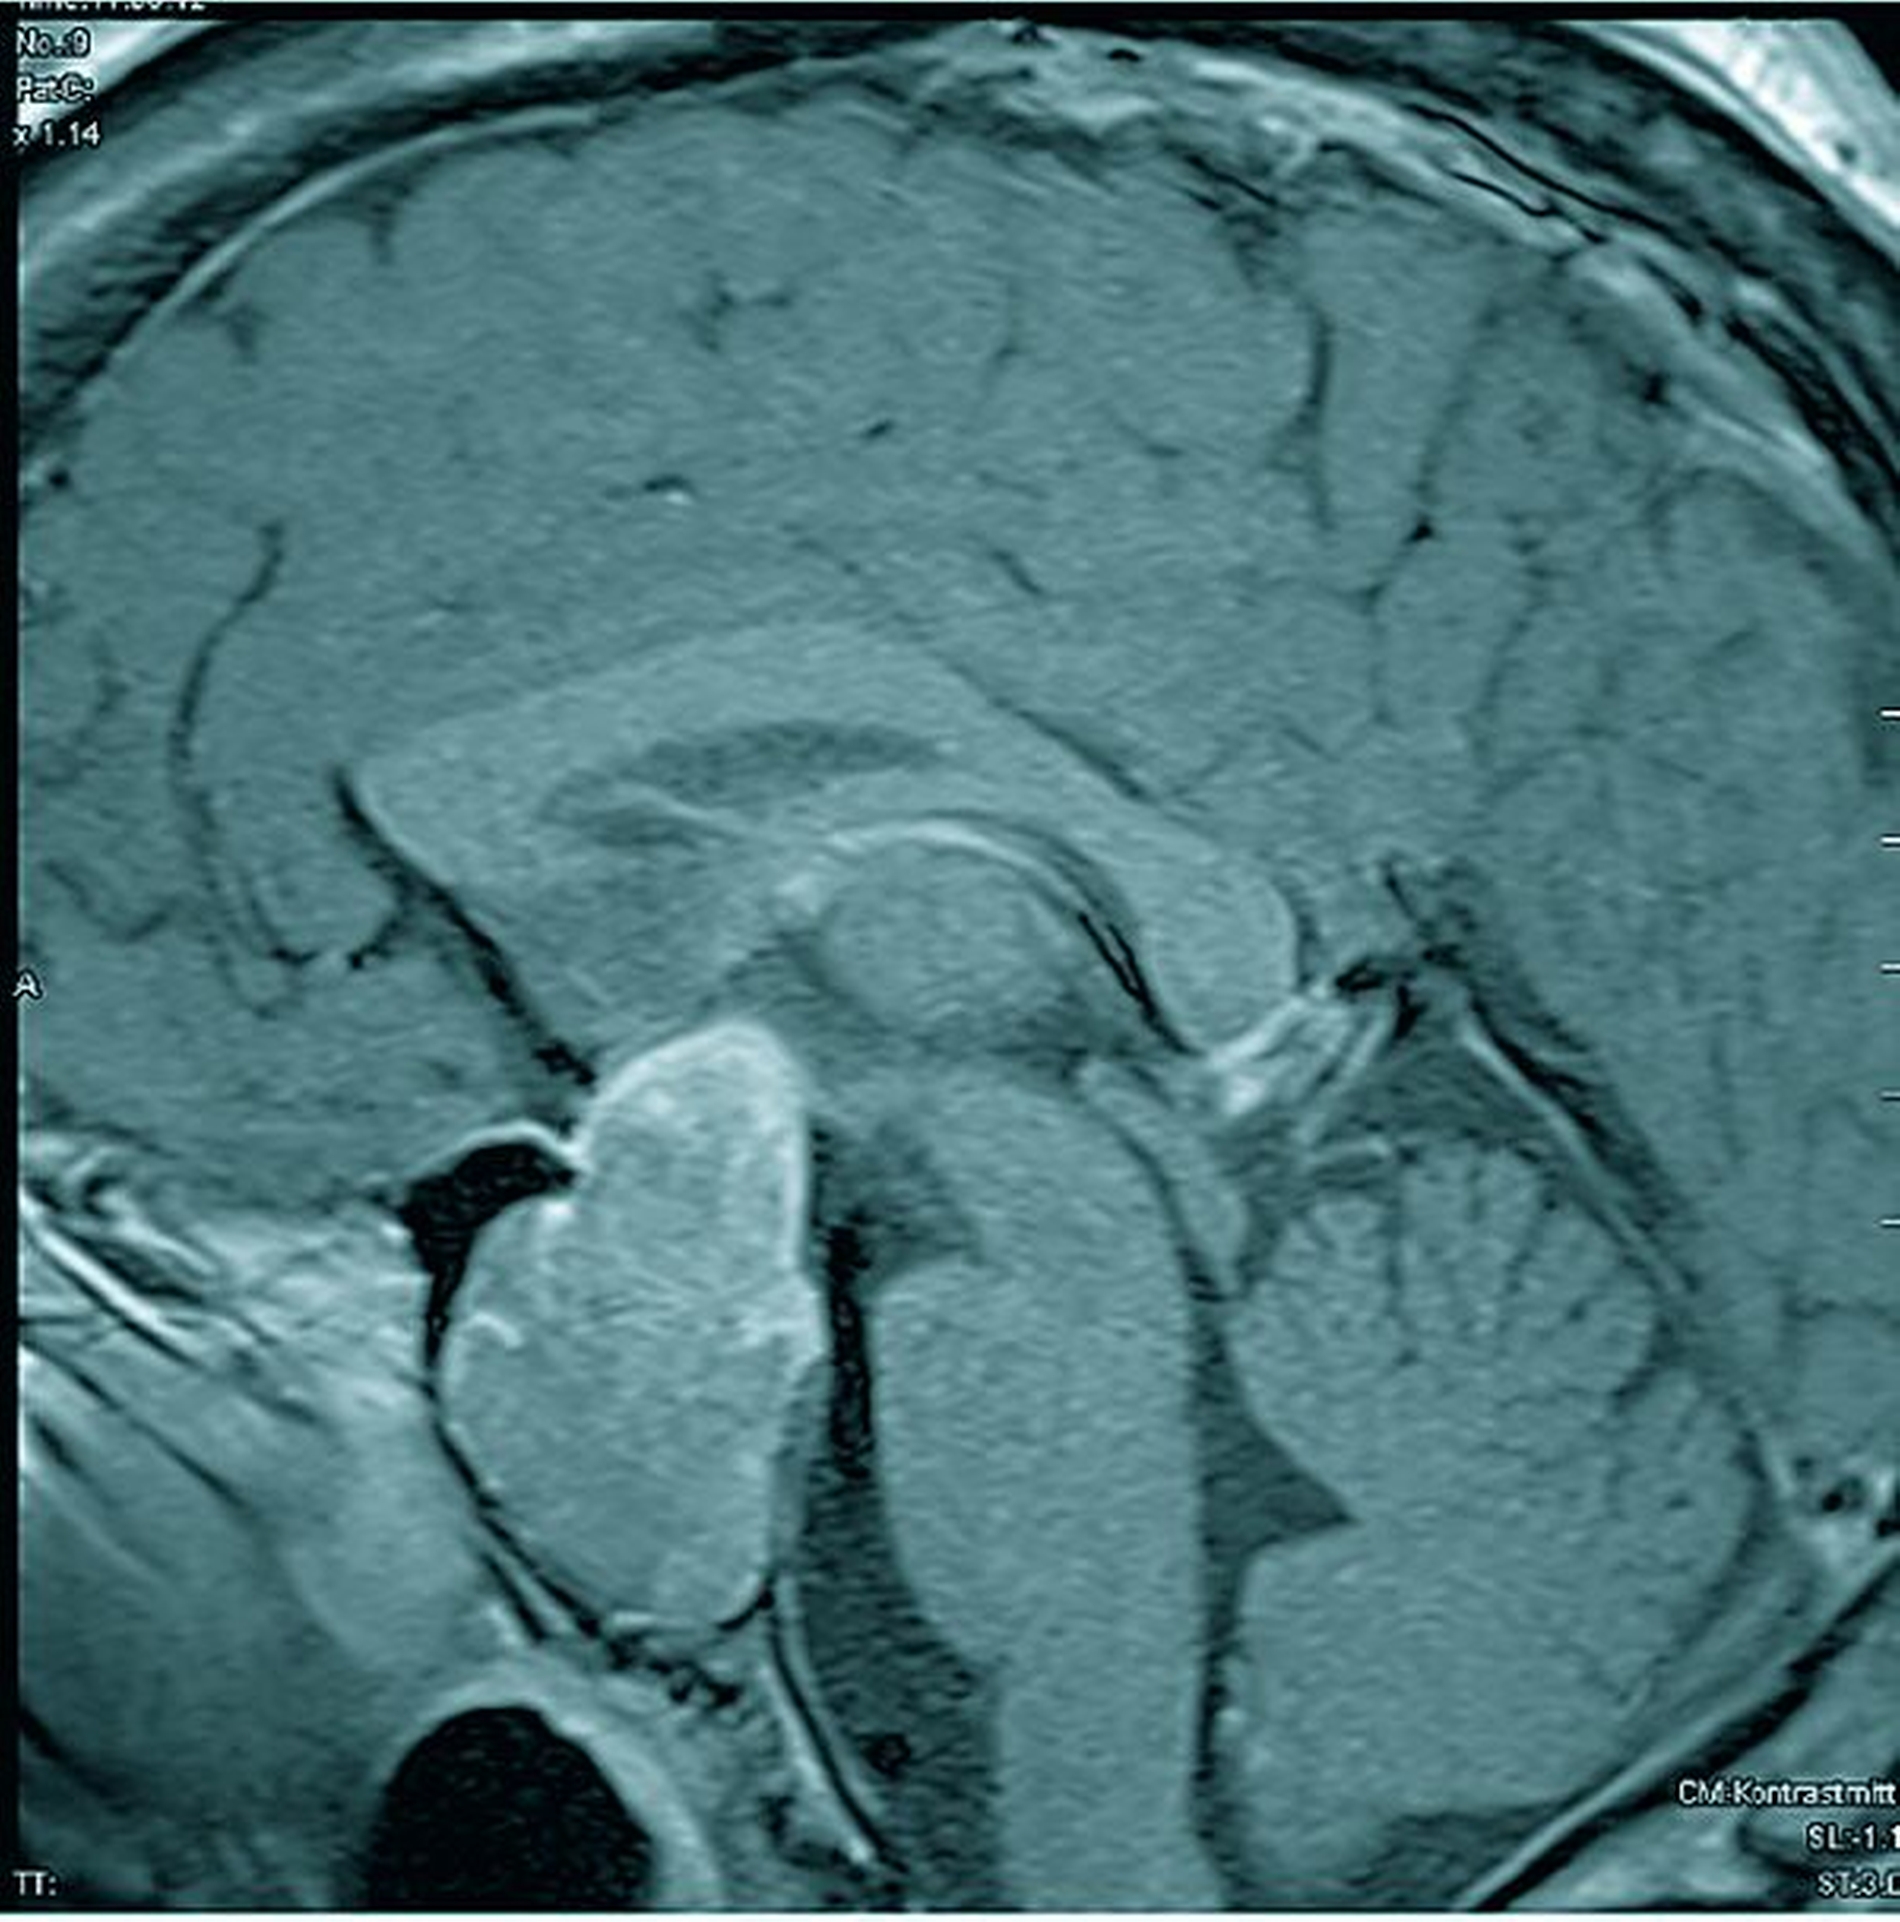

Das angefertigte Fernröntgenseitbild ließ eine massive mandibuläre Prognathie, prominente Supraorbitalwülste und eine stark vergrößerte Sella turcica erkennen (Abbildung 6). Aufgrund des Verdachts einer Akromegalie wurde eine Magnetresonanztomographie veranlasst, in der sich ein intra- und supra sellärer Hypophysentumor von 4,7 x 2,9 x 2,2 cm3 Größe darstellte. Zudem untermauerte eine deutliche Verdickung der gesamten Schädelkalotte die Diagnose Akromegalie (Abbildungen 7 und 8).